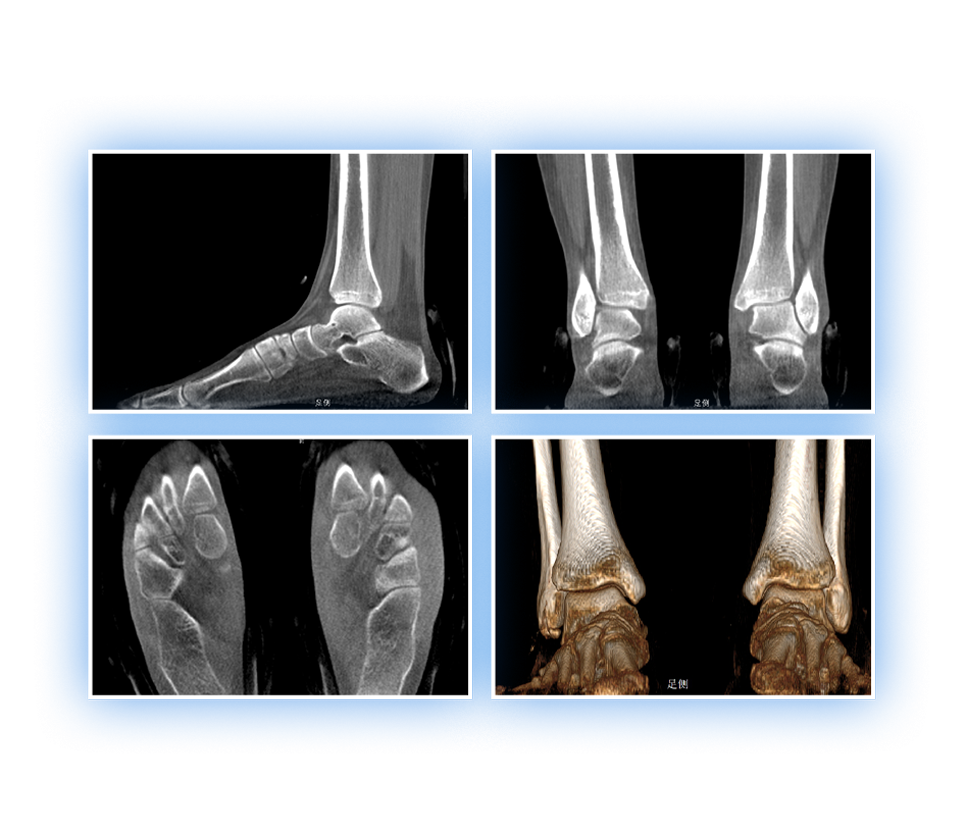

足踝

精準診斷

手術方案規劃

術后隨訪

VR體繪制重建